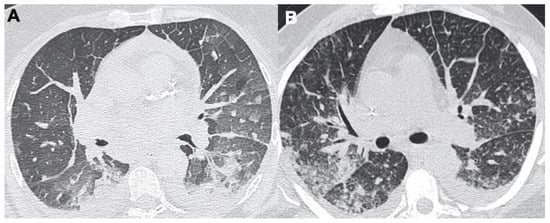

2. COVID-19 and Lung Disease

2.1. Pneumonia

2.2. Acute Respiratory Disease Syndrome